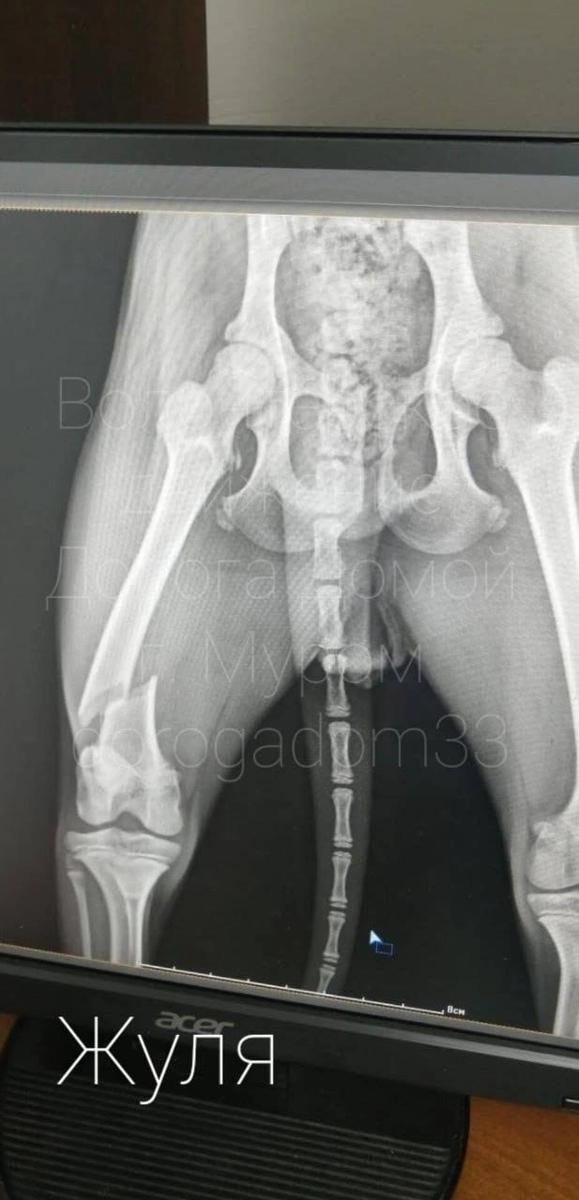

В данный момент Жуля находится в стационаре. У нее взяли анализ крови, сделали рентген. По его результатам у Жули перелом бедренной кости. Нужен остеосинтез, а это дорогостоящая операция. Подготовка к операции, анализы, реабилитация - все это стоит немалых денег. Без Вашей помощи мы бессильны!